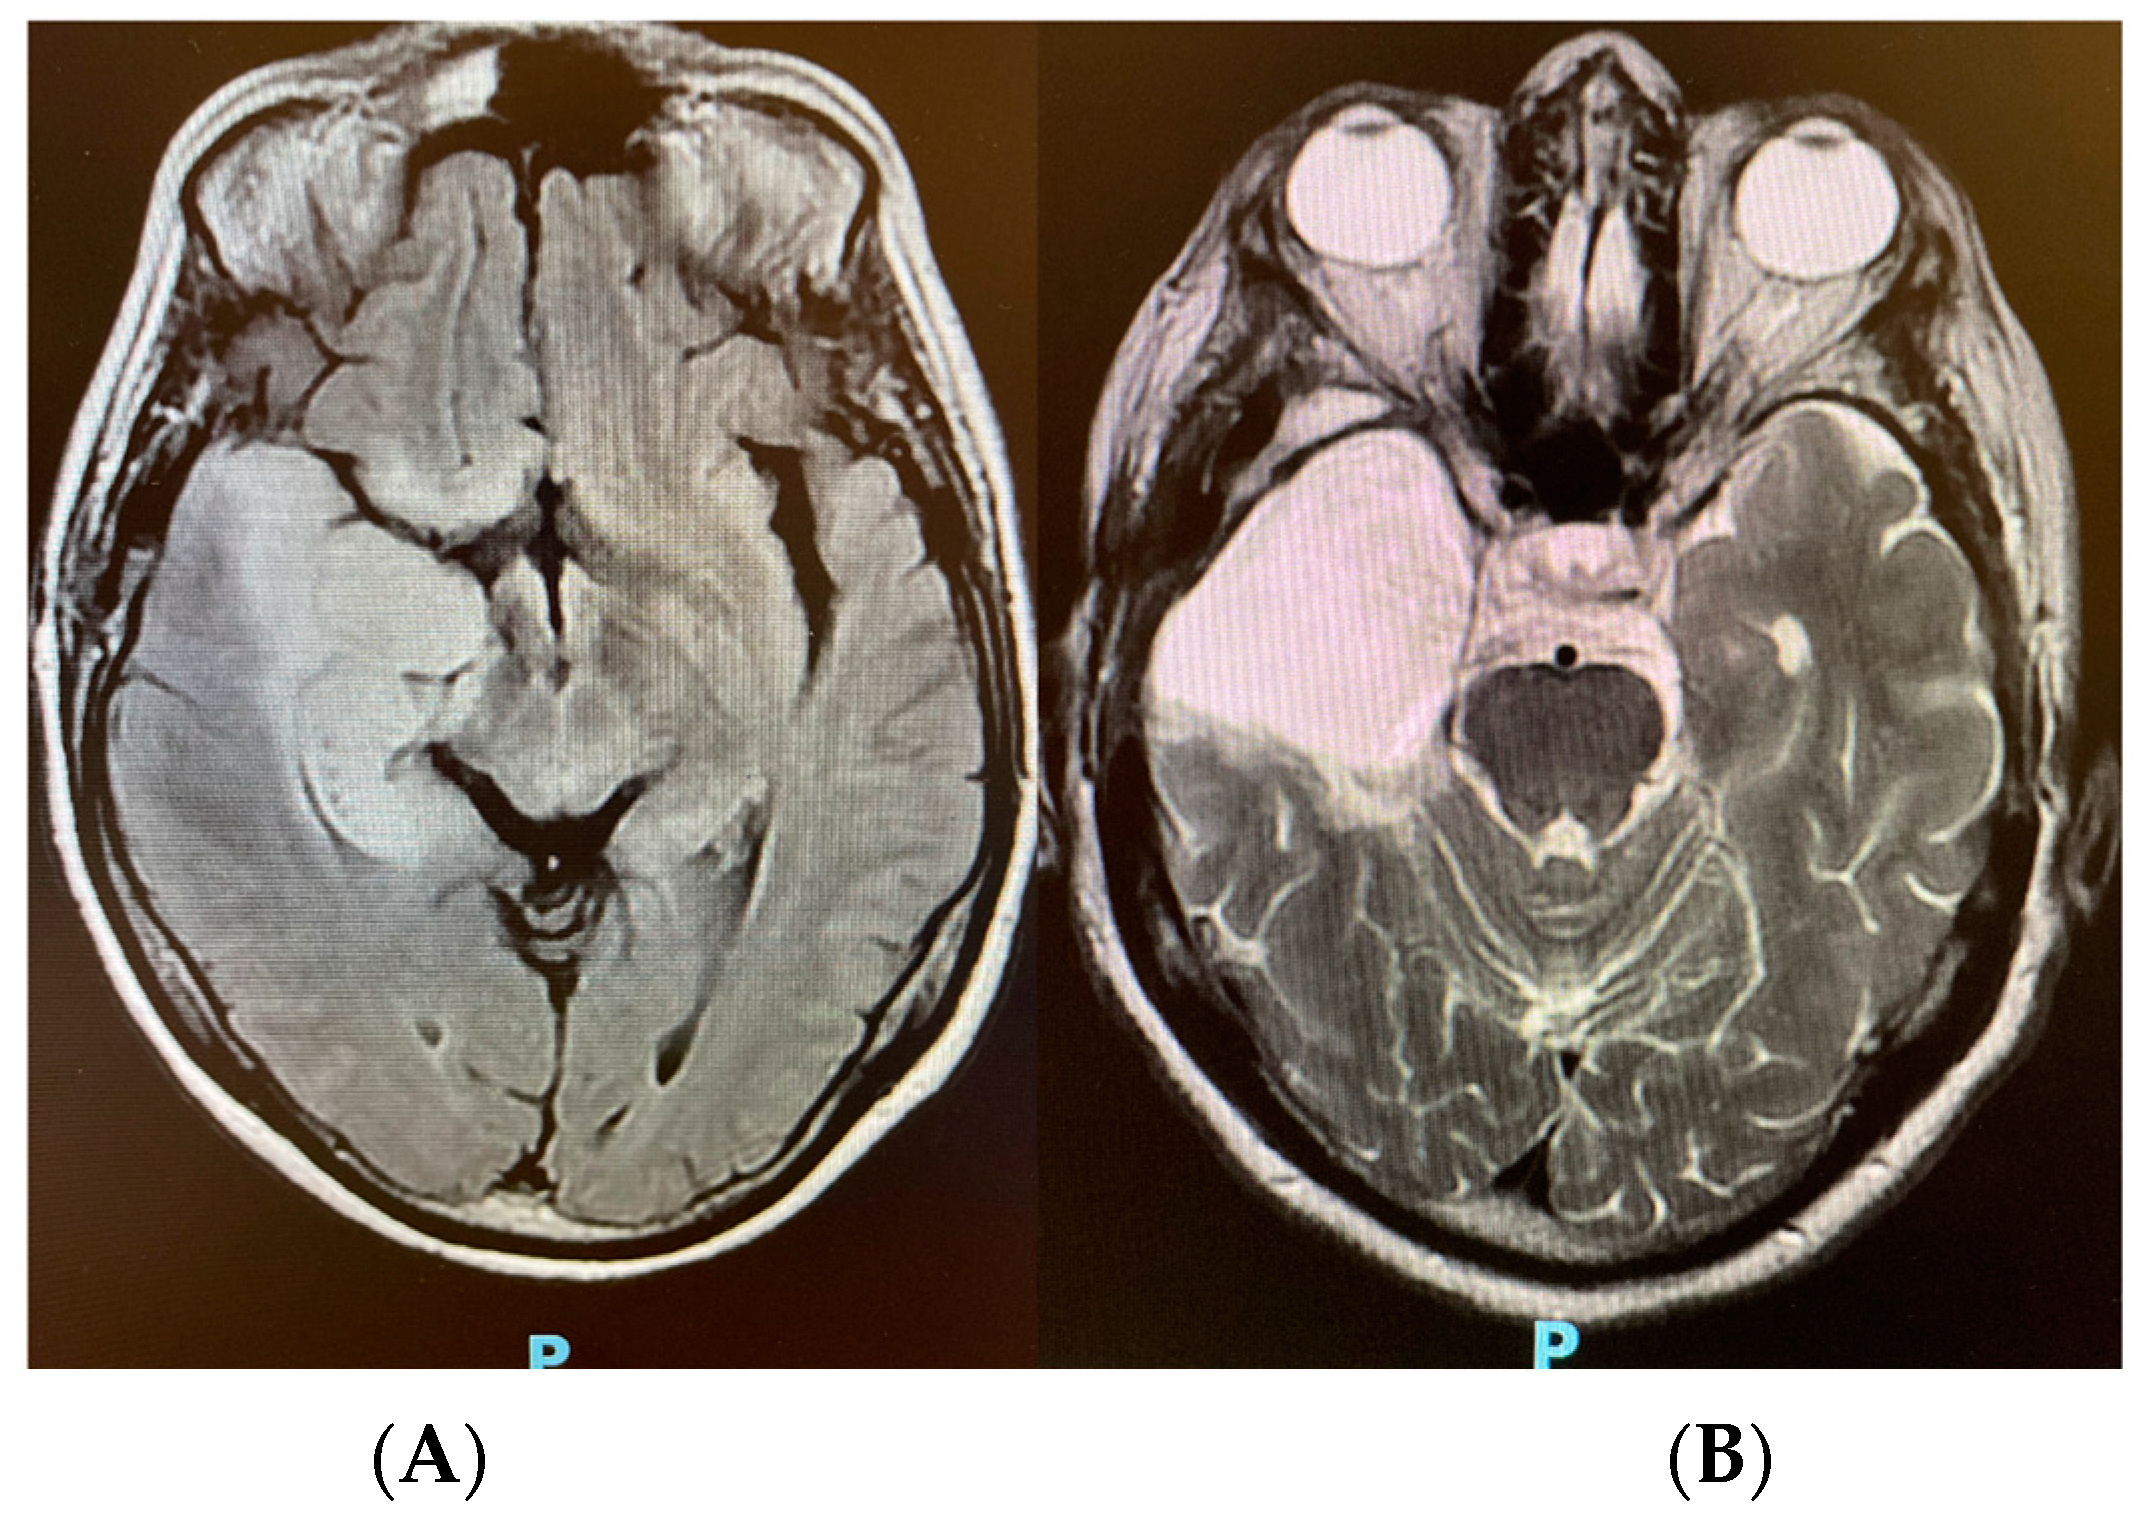

| Date | CSF | ONSD | TCD | B4C |

|---|---|---|---|---|

| D 0 | Pan-herpes negative | |||

| Day 2 | 5.6 mm | MCA 59 cm/s; PI 1.2; RI 0.7 | P2 > P1 | |

| Day 2 | MCA 65 cm/s; PI 1.0; RI 0.5 | P1 > P2 | ||

| Day 5 | Pan-herpes negative |